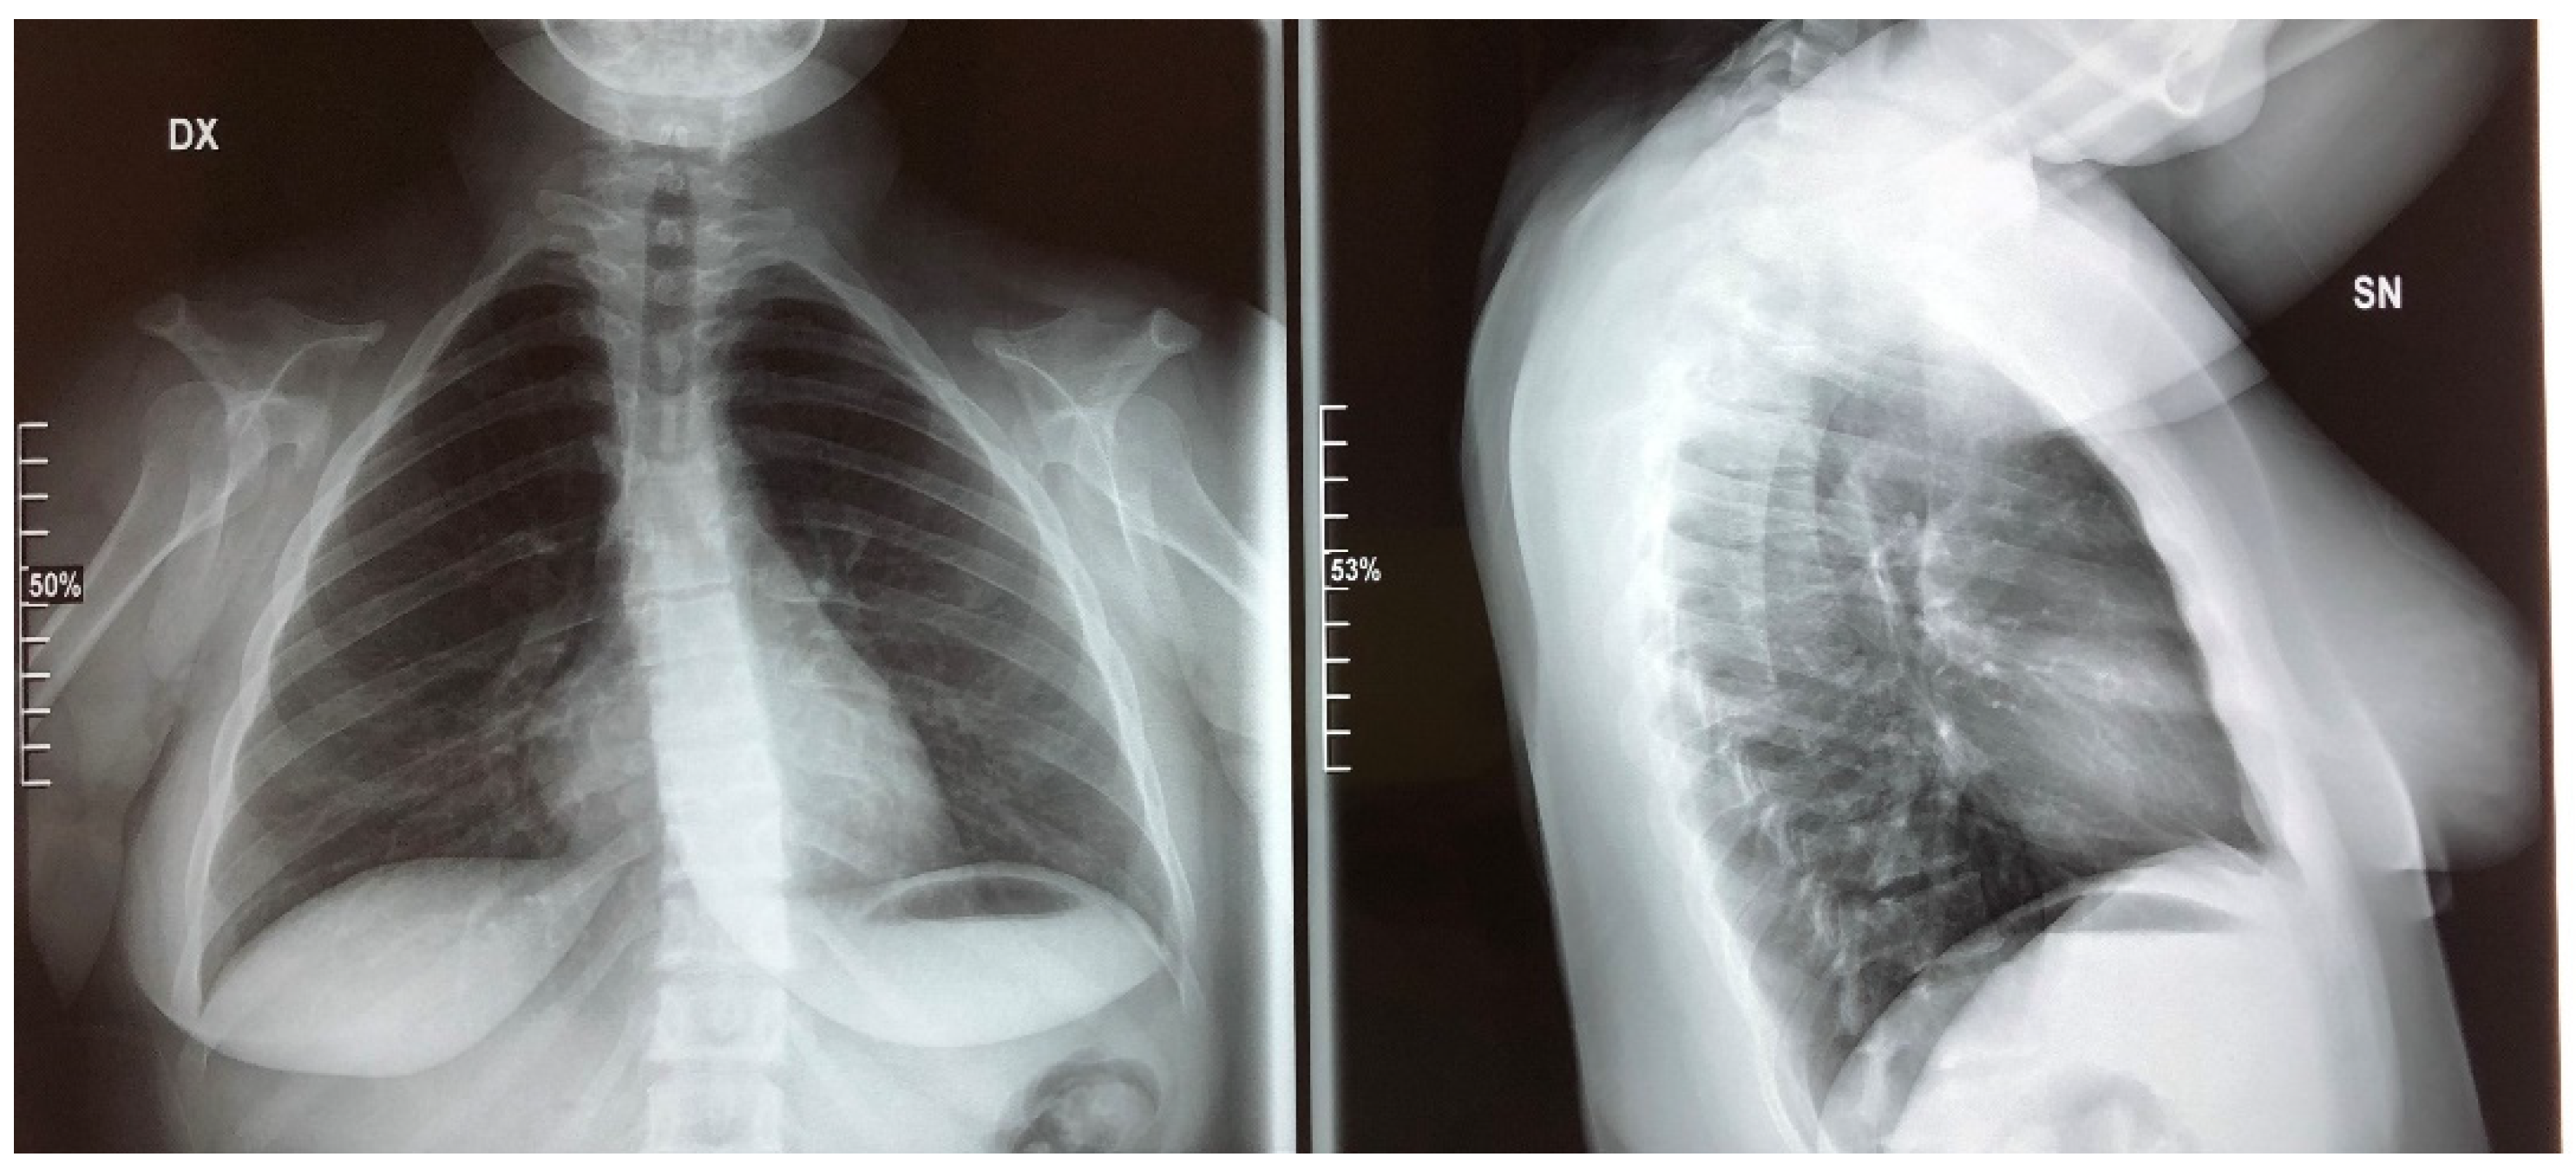

2. Clinical Report